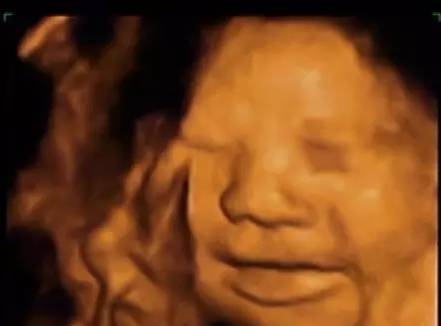

20周胎儿四维真实图片,怀孕20周宝宝真实图片

看看上图是不是很可爱,再看看20周的胎儿动态的四维彩超的表情: 新

四维彩超,原来胎儿是这样的!